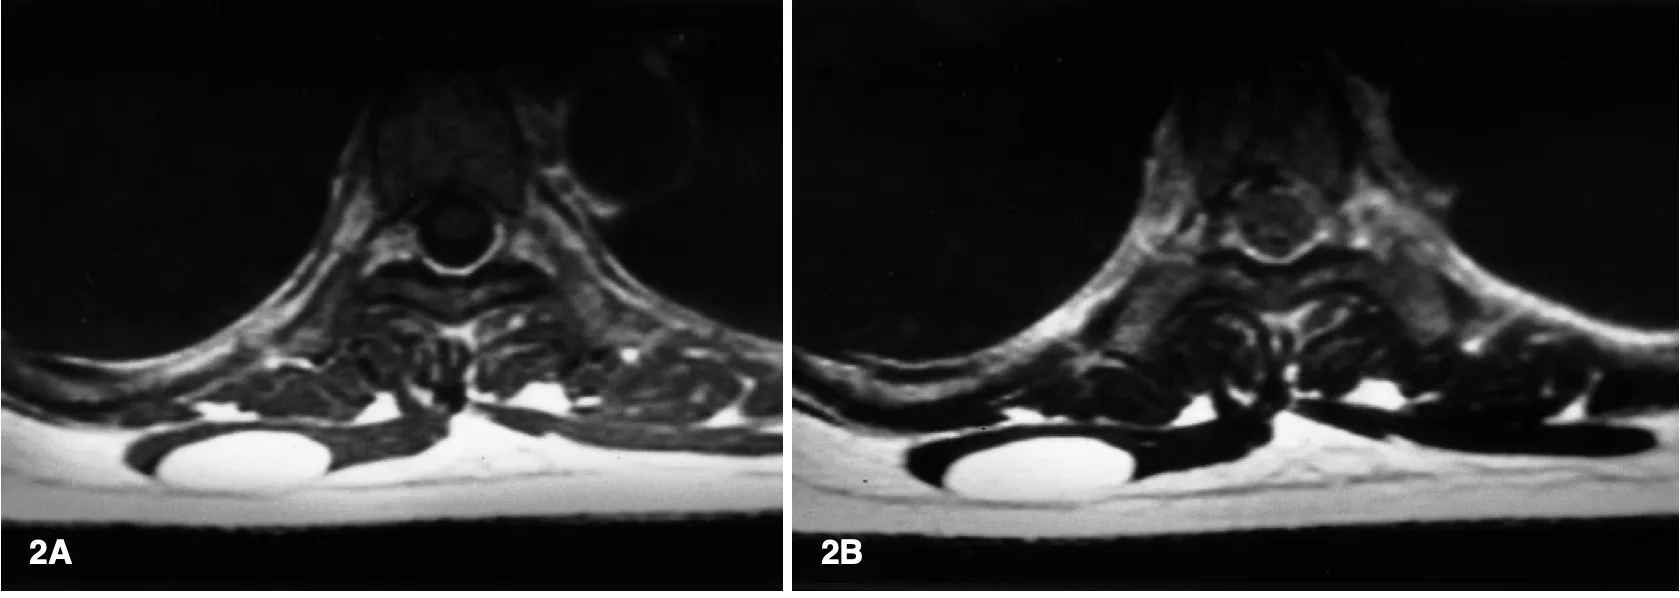

右の僧帽筋の中に皮下脂肪と同じく白く写る楕円形の腫瘍が認められます.

引用元:Matsumoto K. MRI findings in intramuscular lipomas. Skelt Radiology. 1999. 28.

2件目は, 背部の僧帽筋内に発生した脂肪腫の摘出術.